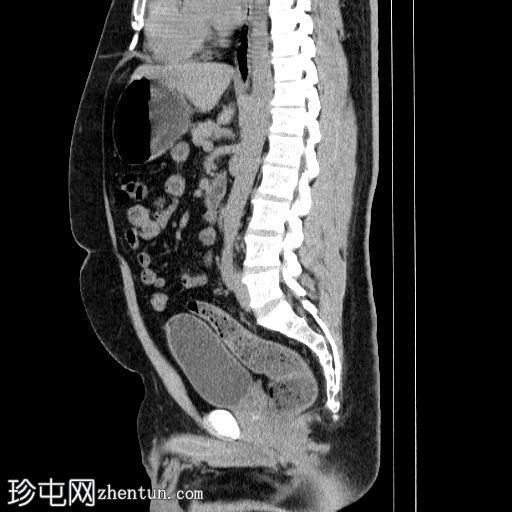

冠状位

平扫

左侧肾盂输尿管连接部(PUJ)可见一枚较大的不透射线结石,最大直径达24 mm,平均CT值约为1160 HU。该结石引起反压改变,导致明显的左肾积水。

此外,左肾中极肾盏内可见一枚直径约13 mm的非梗阻性不透射线结石,平均CT值为1100 HU。

另外,左肾下极肾盏内可见多枚聚集性不透射线结石,总直径约20 mm,平均CT值约为1140 HU。

偶然发现的异常包括前列腺内多发粗大钙化灶,主要位于尿道周围,并伴有轻度肝肿大。